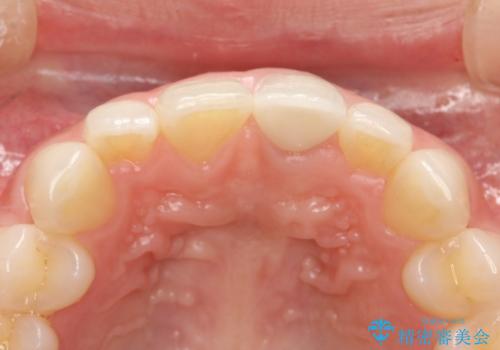

前歯のかぶせ物の色があっていない オールセラミック治療

- 以前装着された前歯のかぶせ物の色を変えたいとのことで来院されました。

土台からの再治療を行い、オールセラミッククラウンを装着する治療計画としました。